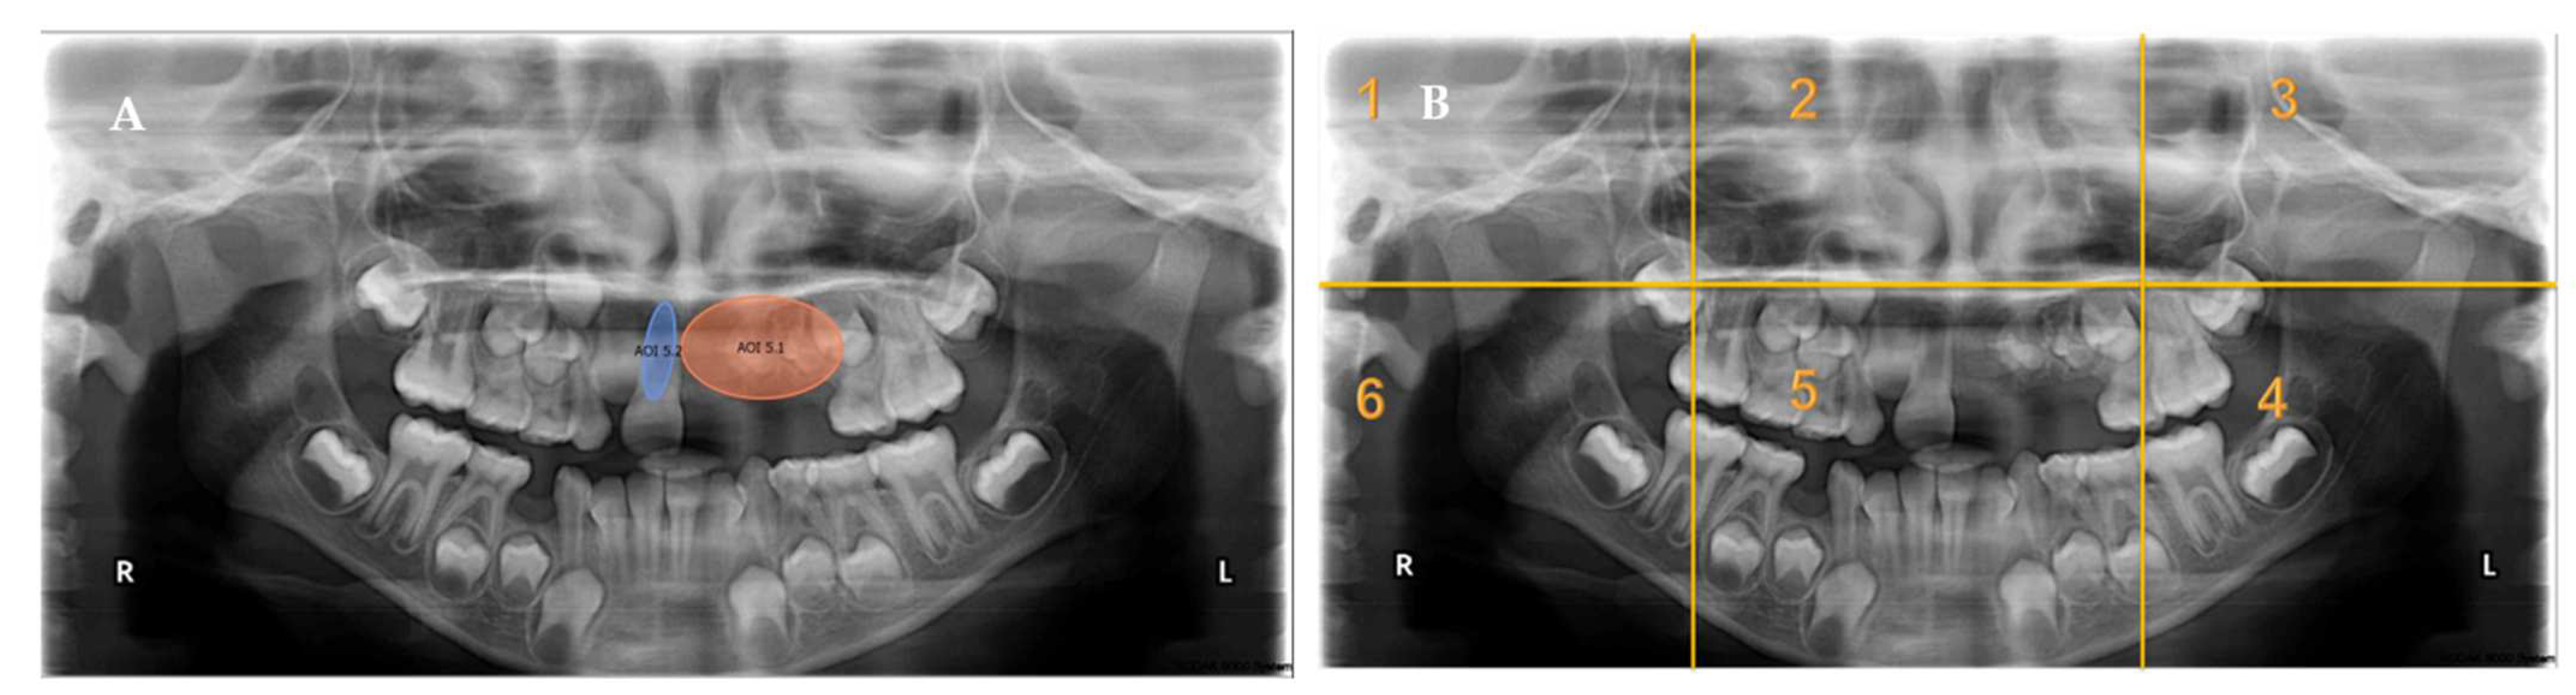

- Each panoramic radiograph displayed will be divided into sextants by yellow lines.

Appendix A. Radiographs Included in the Study